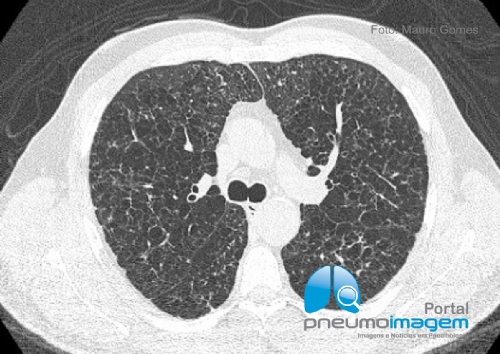

CASO CLÍNICO #56Homem de 48 anos, tabagista e que se apresenta com dispneia. Qual o diagnóstico? Deixe seus comentários abaixo.

A 48-year-old male smoker with dyspnoea. What is the diagnosis? Write your comments below.